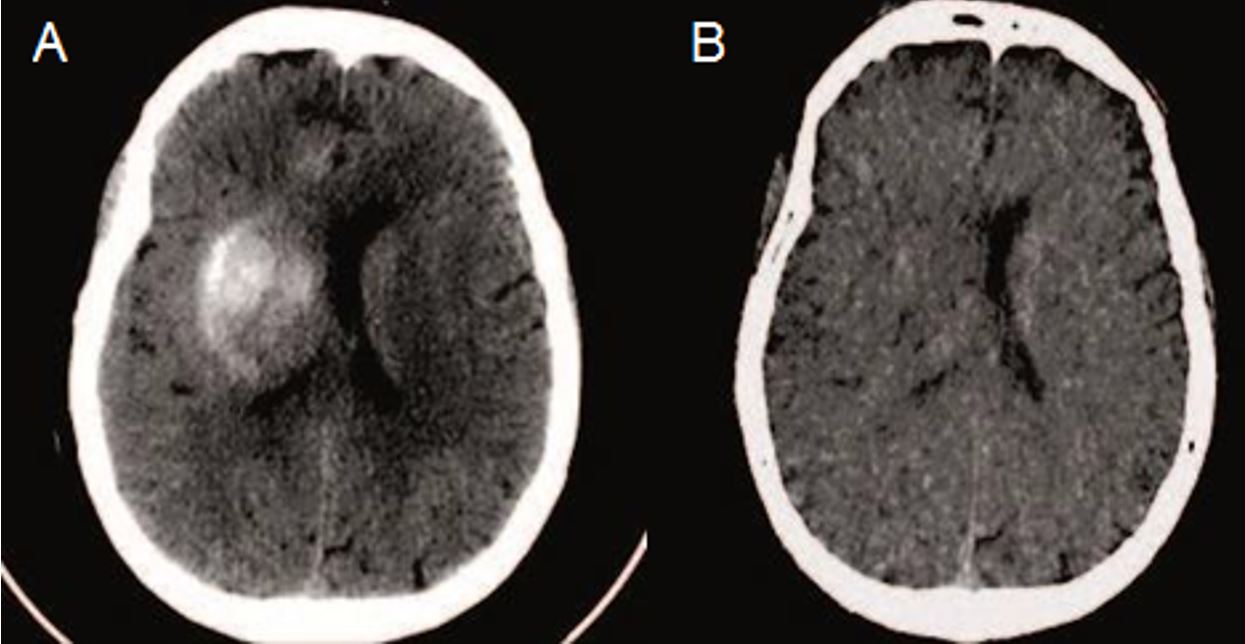

Hình 2. Hình ảnh chụp CLVT sọ não đánh giá sau can thiệp mạch 6 giờ

Trên hình 2 là hình chụp CLVT sọ não đánh giá sau can thiệp mạch 6 giờ, thấy tăng tỷ trọng ở hạch nền bên phải gây hiệu ứng khối (hình A), nghi ngờ chuyển dạng chảy máu. Trên máy chụp CLVT Revolution CT 512 dãy, cũng có thể sử dụng hình ảnh ảo i-ốt tự do (iodine-free virtual imaging - VNC), vùng tăng tỷ trọng biến mất hoàn toàn (hình B), tương ứng với sự hấp thu thuốc cản quang do sự phá vỡ hàng rào máu - não trong quá trình đột quị.